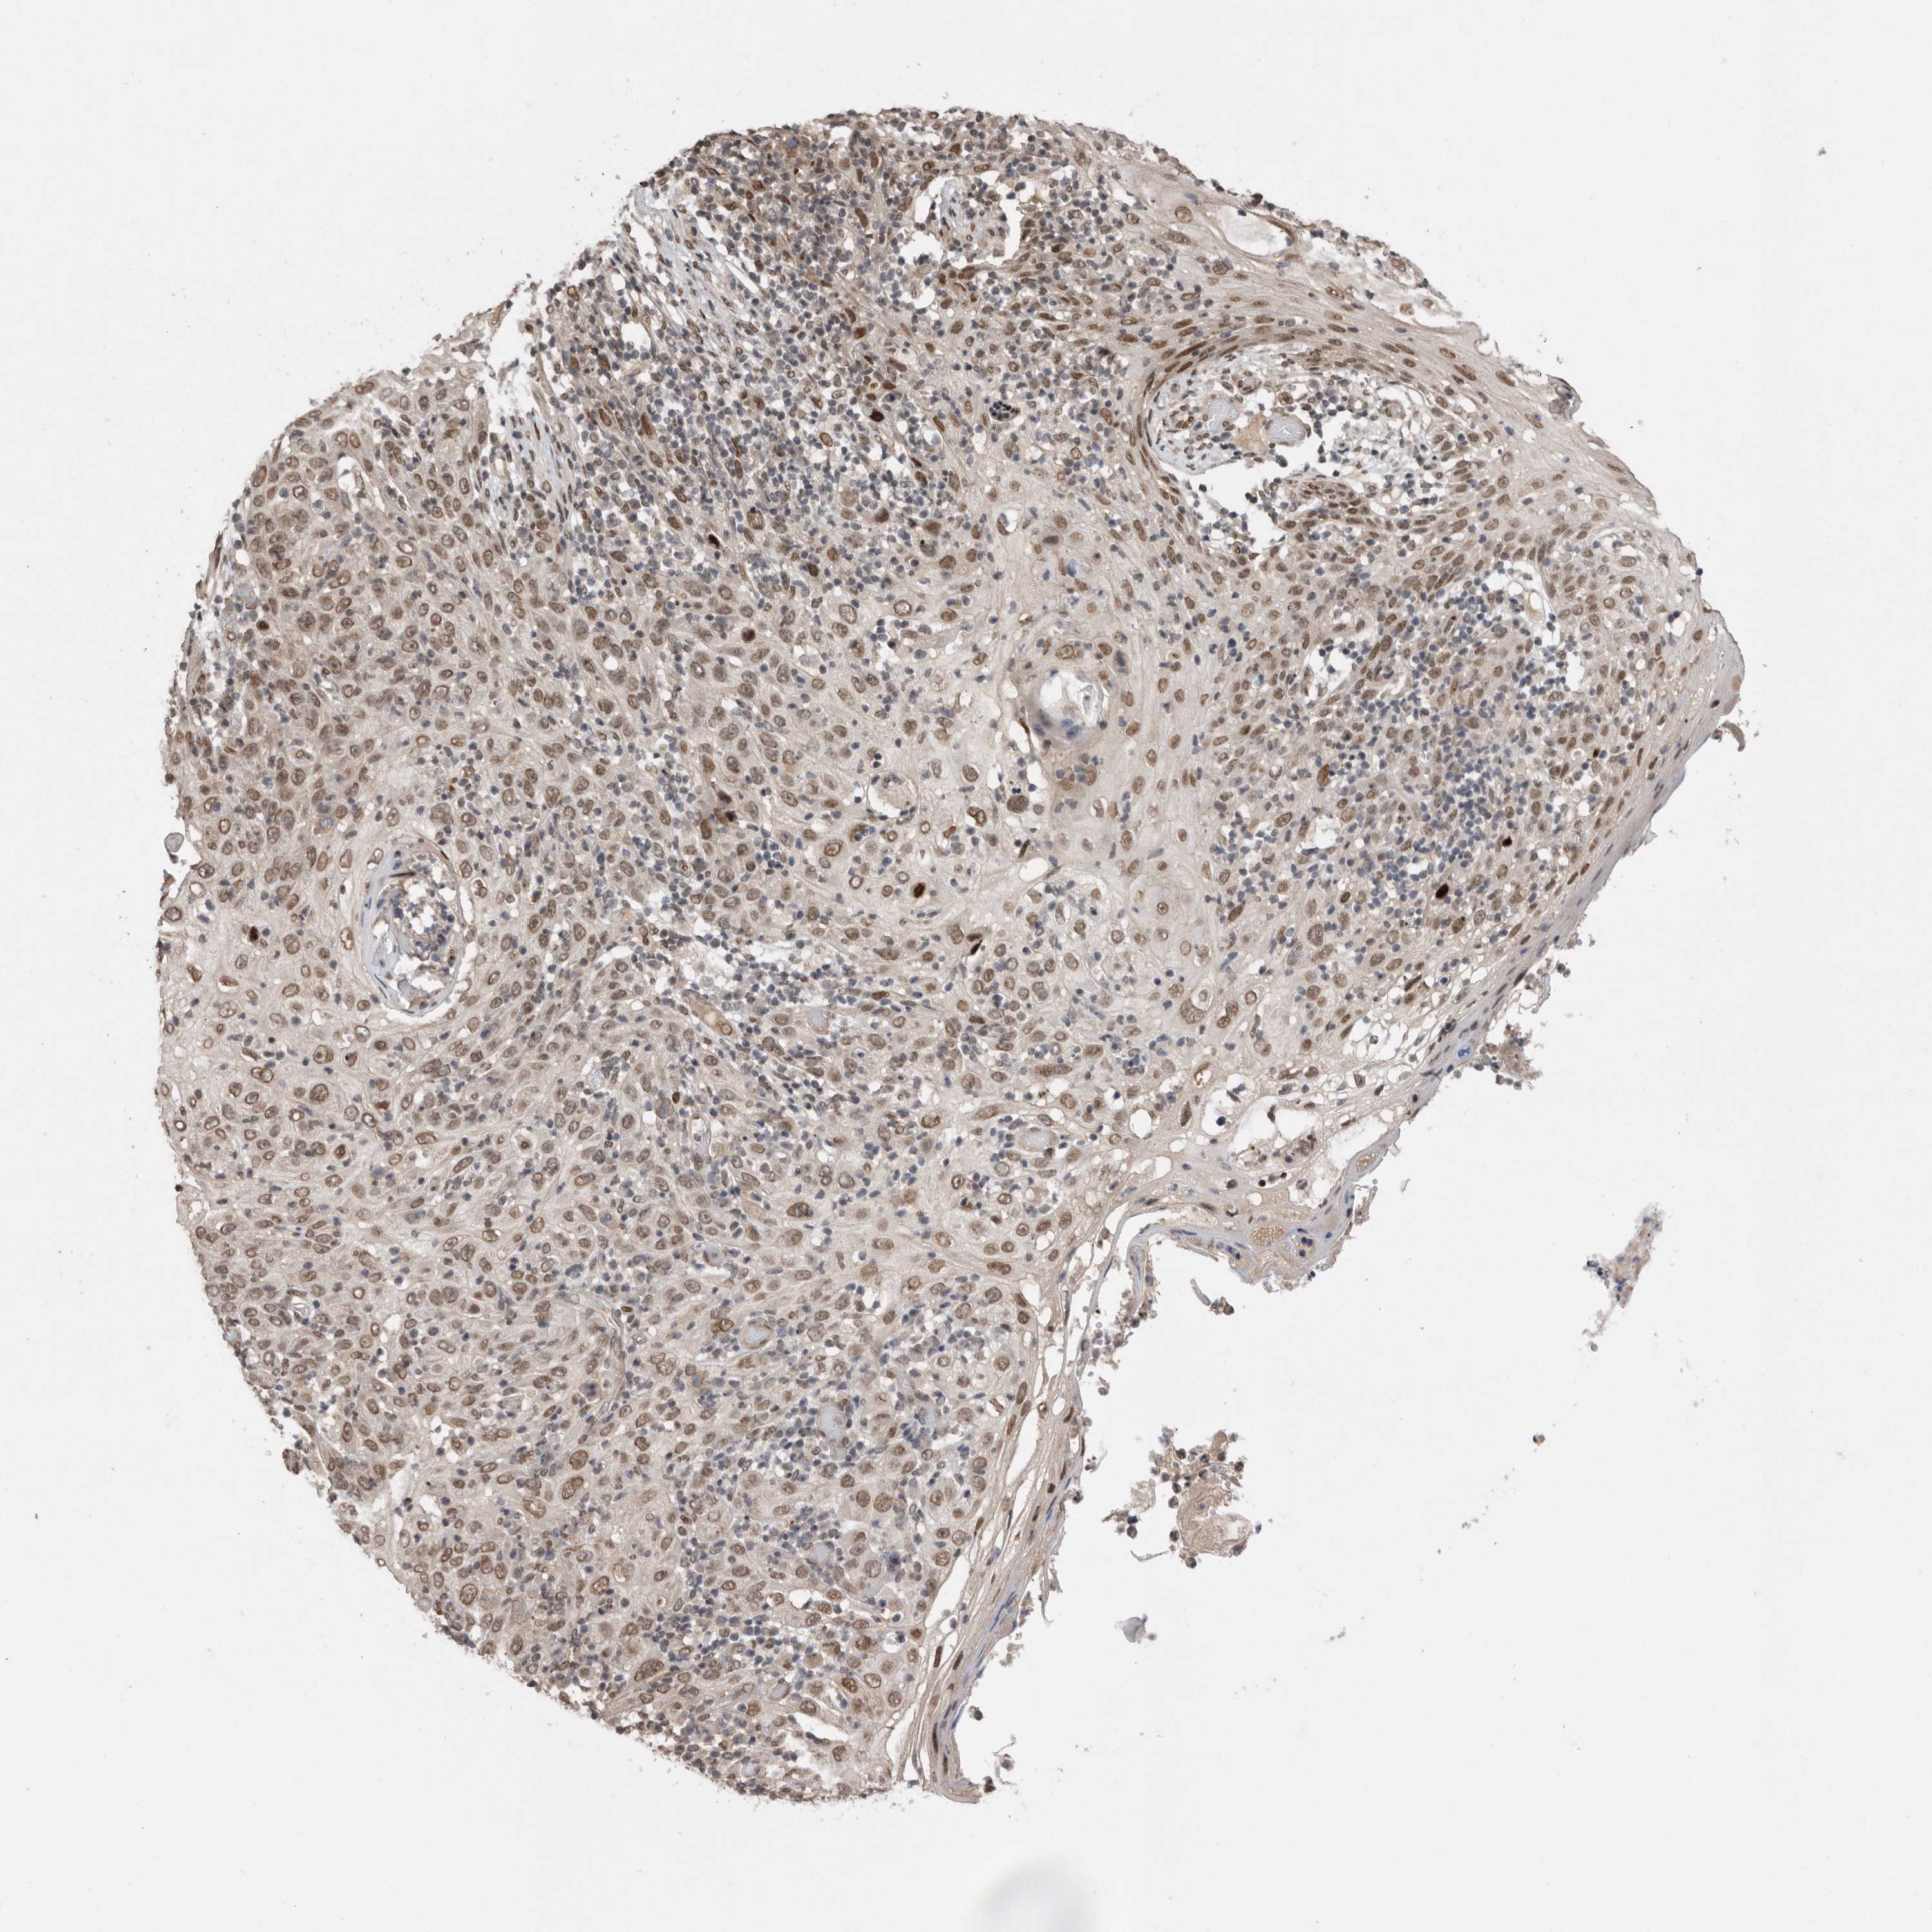

Basal cell and squamous cell cancer

SKIN CANCER - Protein expressioni

A mouse-over function shows sample information and annotation data. Click on an image to view it in a full screen mode. Samples can be filtered based on level of antibody staining by selecting one or several of the following categories: high, medium, low and not detected. The assay and annotation is described here.

Antibody stainingi

Antibody staining in the annotated cell types in the current human tissue is reported as not detected, low, medium, or high, based on conventional immunohistochemistry profiling in selected tissues. This score is based on the combination of the staining intensity and fraction of stained cells.

Each image is clickable and will lead to virtual microscopy that enables deeper exploration of all samples and also displays staining intensity scores, fraction scores and subcellular localization as well as patient and tissue information for each sample.

Antibody CAB034925

Staining

High

Intensity

Strong

Quantity

>75%

Location

Nuclear

Basal cell carcinoma